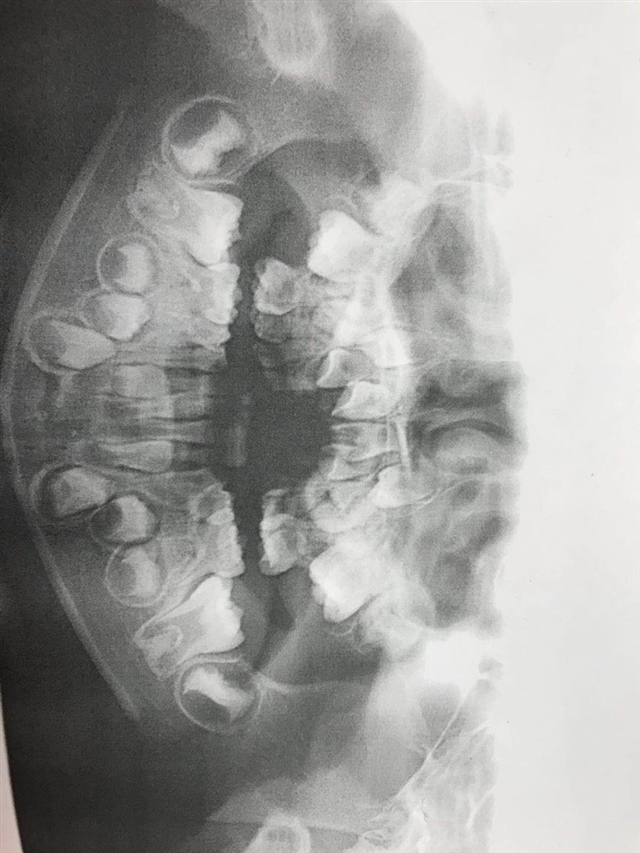

是的,蛀一个烂一口。不要指望换牙!!换牙的时候都是一个个换,挨在一起的还是会蛀。口腔健康真的很重要。可惜不是所有父母都能意识到。良好的习惯必须从小抓起。